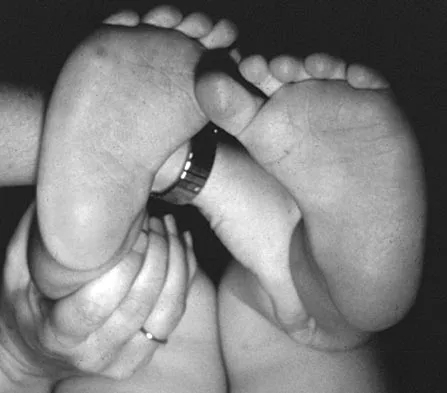

Figure 16 shows the clinical photograph of a 3-month-old infant with a foot deformity that has been nonprogressive since birth. Examination reveals that the deformity corrects actively and with passive manipulation. There is no associated equinus. Management should consist of